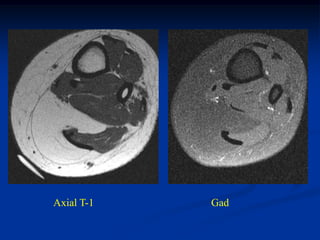

Case #309

Coronal T-1 MRI

45 year male with hemangiopericytoma thigh

Axial T-1 MRI

Axial proton density MRI

tumor

Axial T-2 MRI

Case #309 Coronal T-1 MRI 45 year male with hemangiopericytoma thigh

• 420.

• 421.

• 422.

tumor Axial T-2 MRI